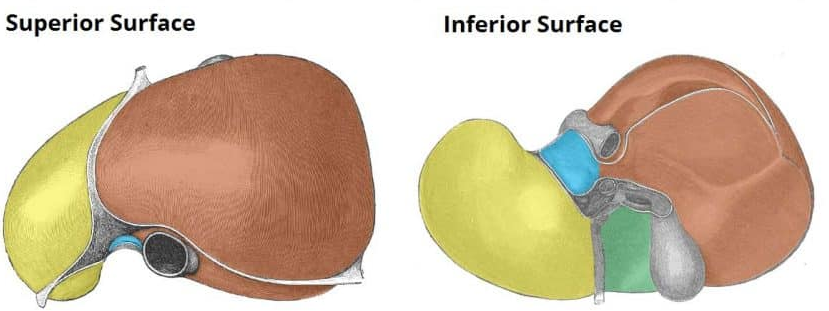

Right liver lobe

orange highlight

Left liver lobe

yellow highlight

Falciform ligament

Coronary ligament

Round ligament

Caudate lobe

blue highlight

Quadrate lobe

green highlight

Porta hepatis

What do all these make up (this is the posterior liver)

Inferior vena cava

Hepatic artery

Hepatic portal vein